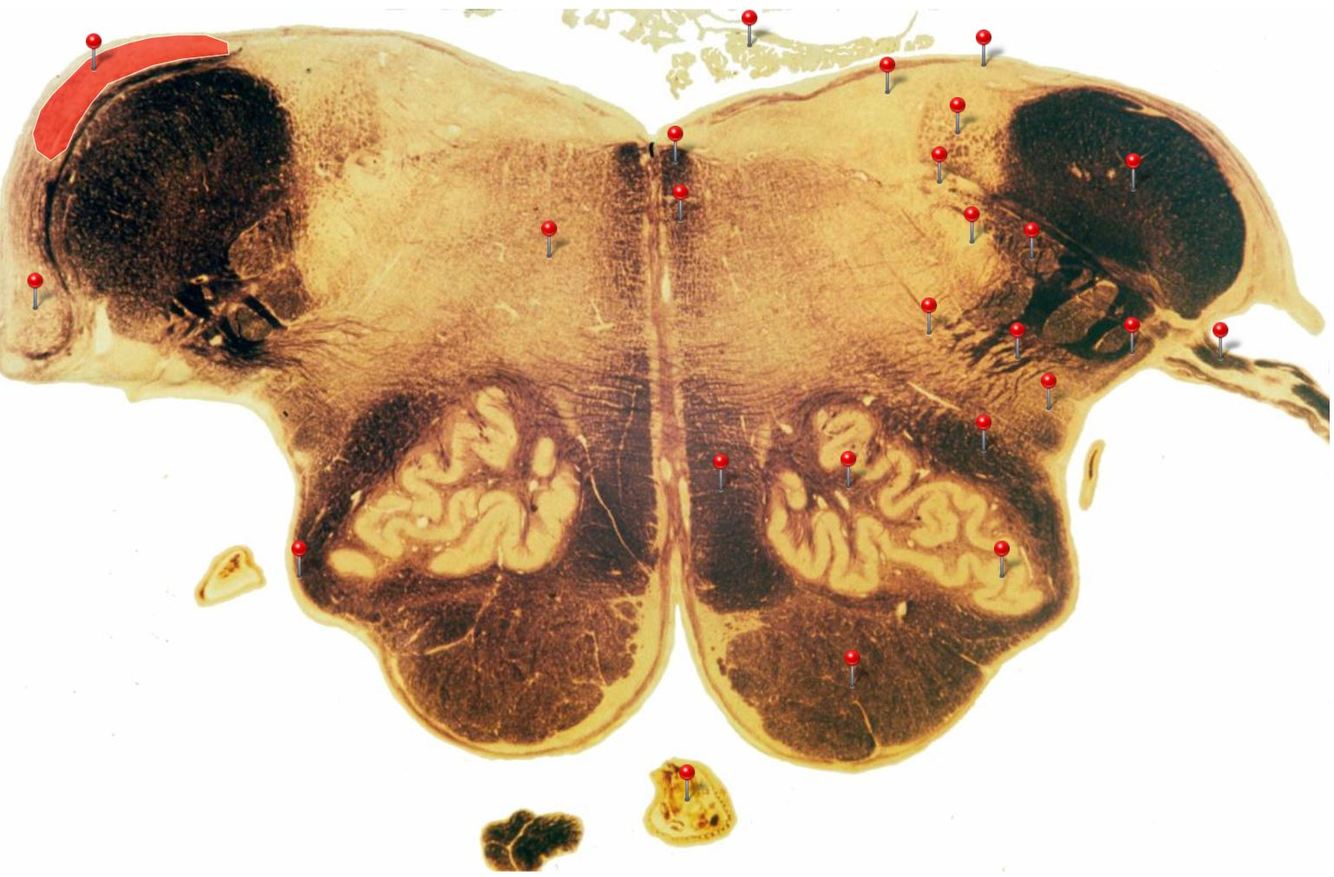

Corticospinal Tract

Rostral Medulla

Controls precision and speed of skilled movements involving the distal muscles of the contralateral limbs, particularly those of the hands and fingers

Nucleus Ambiguus

Neurons supply the muscles of the pharynx, larynx, upper oesophagus and heart

Basilar Artery

Provides blood supply to much of the cerebellum, pons, midbrain and posterior thalamus as well as part of the temporal (inferior surface) and occipital (medial and inferior surfaces) lobes

Olives

Elevations formed by the inferior olivary nuclei which integrate information from a variety of sources before relaying it to the cerebellum

Rubrospinal Tract

Assists in the control of movements of the hands and fingers

Medial Vestibular Nucleus

Process inputs from vestibular receptors of the inner ear and are involved in the regulation of posture and the coordination of head and eye movements

Spinal Trigeminal Tract

Transmits somatosensory (crude touch, pain and temperature) inputs from the Trigeminal nerve (CN V) through the midpons and medulla to the spinal trigeminal nucleus.

Ventral Cochlear Nuclei

One of the relay nuclei for the auditory fibres of the vestibulocochlear nerve (CN VIII) and functions to modify inputs to the higher auditory structures

Medial Longitudinal Fasciculus

Pathway through which eye movements are coordinated with changes in head position

Dorsal Cochlear Nuclei

One of the relay nuclei for auditory fibres of the vestibulocochlear nerve (CN VIII) and functions to modify inputs to the higher auditory structures

Inferior Olivary Nucleus

Plays an important role in the learning of new motor skills

Solitary Nucleus

Processes visceral afferent (GVA and SVA [taste]) inputs from CN VII, IX and X and relays them to the reticular formation and visceral efferent nuclei

Spinal Trigeminal Nuclei

Processes sensory inputs, particularly pain and temperature, from the head and neck and relays them to the ventral posteromedial nucleus of the thalamus

Inferior Vestibular Nucleus

Plays a role in the maintenance of balance and the coordination of eye and head movements

Medial Lemniscus Rostral Medulla Transmits sensations of **discriminative touch, vibration, proprioception** an **stereognosis** from the *gracile* and *cuneate nuclei* to the *ventral posterior nuclei of the thalamus*

Ventral Spinocerebellar Tract Rostral Medulla Provides feedback to the cerebellum concerning motor activity (including reflexes) in the lumbosacral levels of the spinal cord

Glossopharyngeal Nerve (CN IX) Rostral Medulla Transmits taste and tactile sensation from the posterior part of the tongue, pharynx and ear, and visceral sensation from the chemo- and baroreceptors of the carotid body and sinus (also supplies efferent fibres to the otic ganglion and stylopharyngeus m.)

Inferior Cerebellar Peduncle Rostral Medulla Formed by pathways passing in both directions between the medulla and cerebellum

Tectospinal Tract Rostral Medulla Function in humans not precisely determined; thought to mediate reflex movements of head in response to visual and perhaps auditory stimuli

Olivocerebellar Tract Rostral Medulla Transmits information from inferior olivary nucleus to the *contralateral* cerebellum, where it forms the **climbing fibres**

Lateral Vestibular Nucleus Rostral Medulla Contains cell bodies of the (lateral) vestibulospinal tract which regulates the activity of **axial** and **proximal** limb muscles in order to **maintain balance and posture**